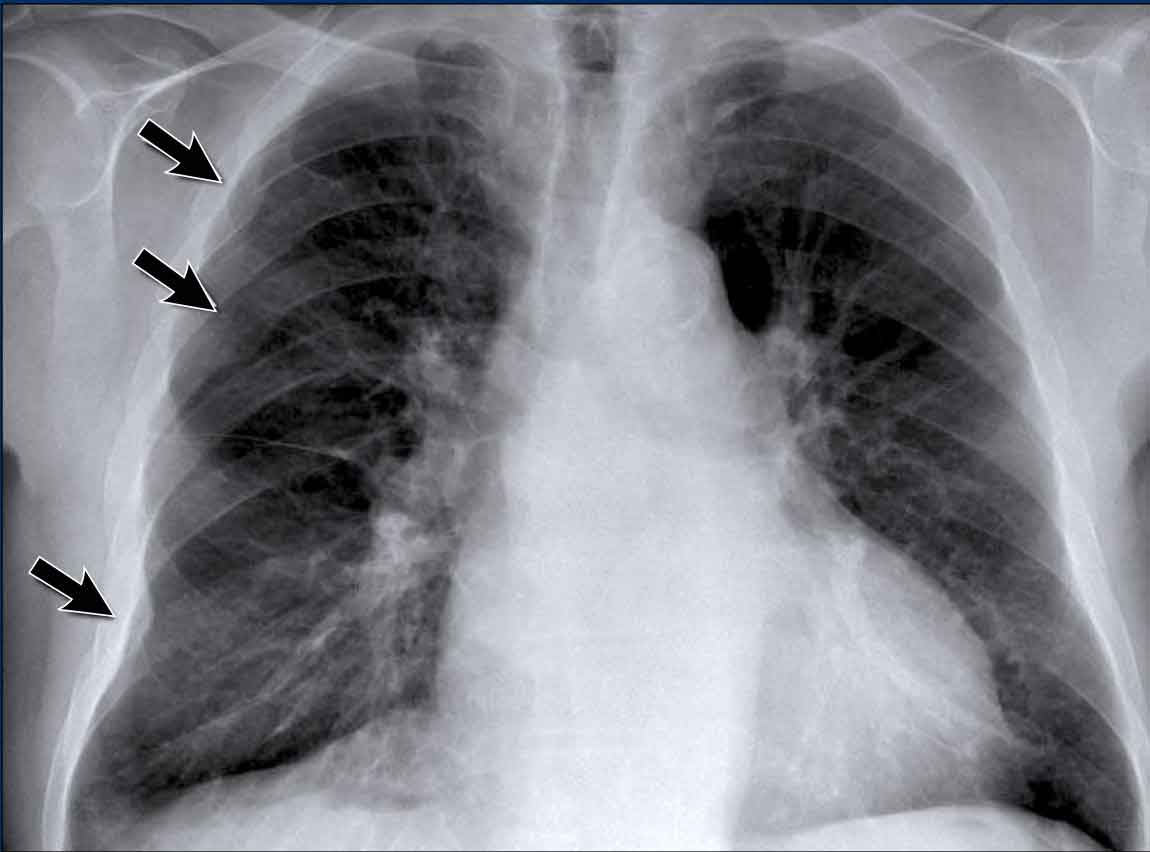

Case Example: Subtle Signs of Congestive Heart Failure

Begin by reviewing these current chest radiographs.

Based solely on these images, one might suspect congestive heart failure (CHF), though the findings are subtle.

Scrolling between the current and prior films significantly increases diagnostic confidence in your diagnosis of congestive heart failure.

Key comparative findings include:

• Cardiac size: Slightly increased compared to the previous study; however, cardiomegaly was already present.

• Pulmonary vasculature: Mild vascular engorgement suggesting elevated pulmonary venous pressure.

• Interstitial markings: Subtle signs of interstitial edema .

• Pleural effusions: Bilateral small effusions, with subtle changes in the inferoposterior borders of the lower lobes, suggesting fluid accumulation.